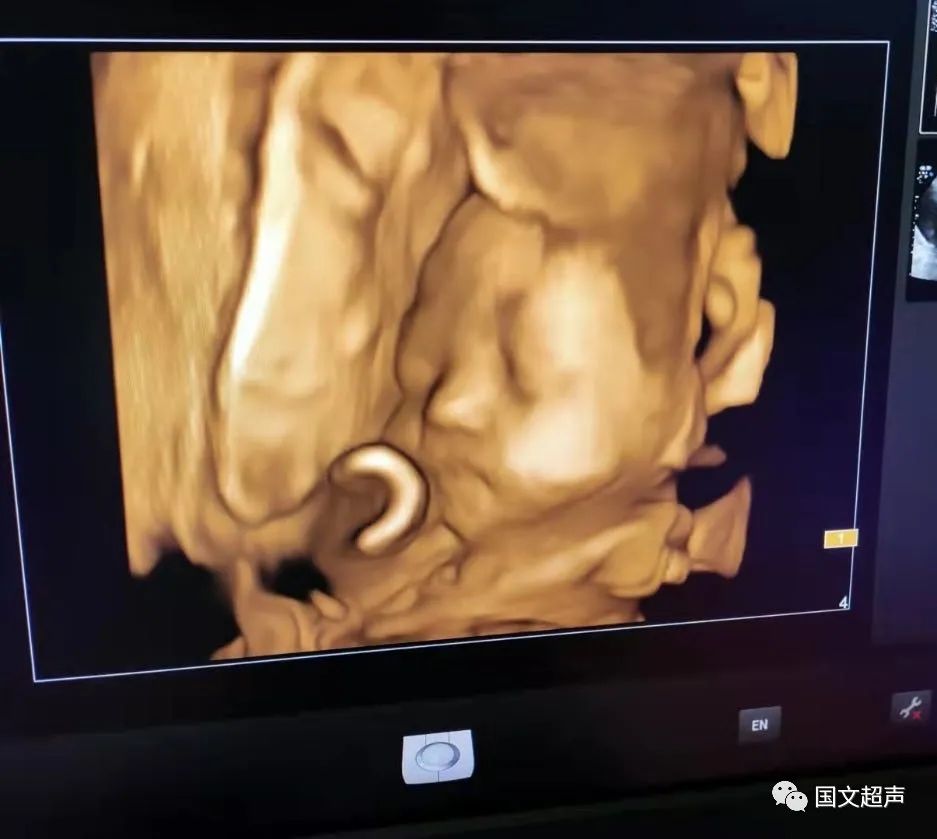

3.孕28周~32周,對孕中期檢查加以補充,因胎兒在發(fā)育過程中,可能存在發(fā)展變化。